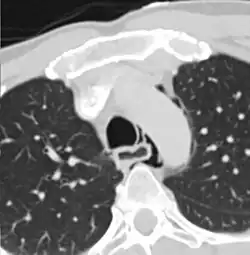

| Axial CT image through the upper chest showing extraluminal air (Pneumomediastinum) surrounding the trachea and esophagus | |

Hours to days later, pleural effusion(s) with or without pneumothorax, widened mediastinum, and subcutaneous emphysema is typically seen. CT scan may show esophageal wall edema and thickening, extraesophageal air, periesophageal fluid with or without gas bubbles, mediastinal widening, and air and fluid in the pleural spaces, retroperitoneum or lesser sac.